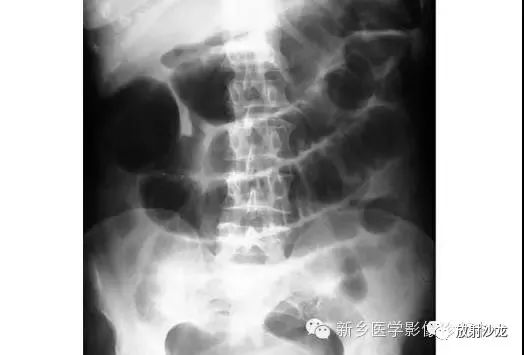

病例一:

上张X线片在小肠靠近横结肠处出现几圈膨大后合并狭窄。术中发现该患者由于肠系膜动脉栓塞致小肠肠襻坏疽。

病人出现腹部不适的明显迹象。大肠梗阻在腹部平片上会表现为什么呢?

结肠扩张是由于粪便嵌塞。大肠可通过结肠袋来识别,并且其从升结肠延续至乙状结肠。由于排泄物挤压致粪便和气体积聚使直肠存留少量气体。这可通过肛门镜检或直肠指诊来确认。